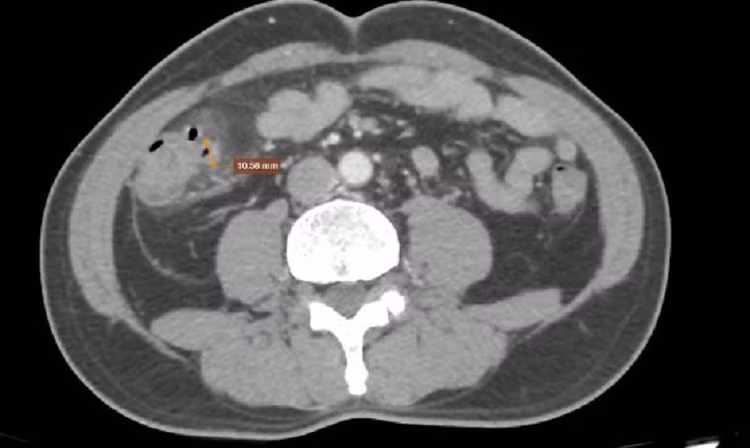

Chụp CT ổ bụng cho hình ảnh đại tràng phải có vài túi thừa, lớn nhất đường kính 10.5mm. Ảnh BVCC

Chụp CT ổ bụng: Phát hiện vài túi thừa ở đại tràng phải (lớn nhất 10.5mm), thành đại tràng dày nhẹ, thâm nhiễm mỡ quanh đại tràng, dày phúc mạc kèm hạch mạc treo (<6mm), ít dịch vùng tiểu khung, đồng thời phát hiện sỏi và nang thận phải. Sau khi có kết quả, bác sĩ xác định bệnh nhân bị viêm túi thừa đại tràng phải kèm theo một số bệnh lý về thận. Người bệnh được tư vấn điều chỉnh chế độ ăn uống, dùng thuốc điều trị viêm và theo dõi định kỳ.